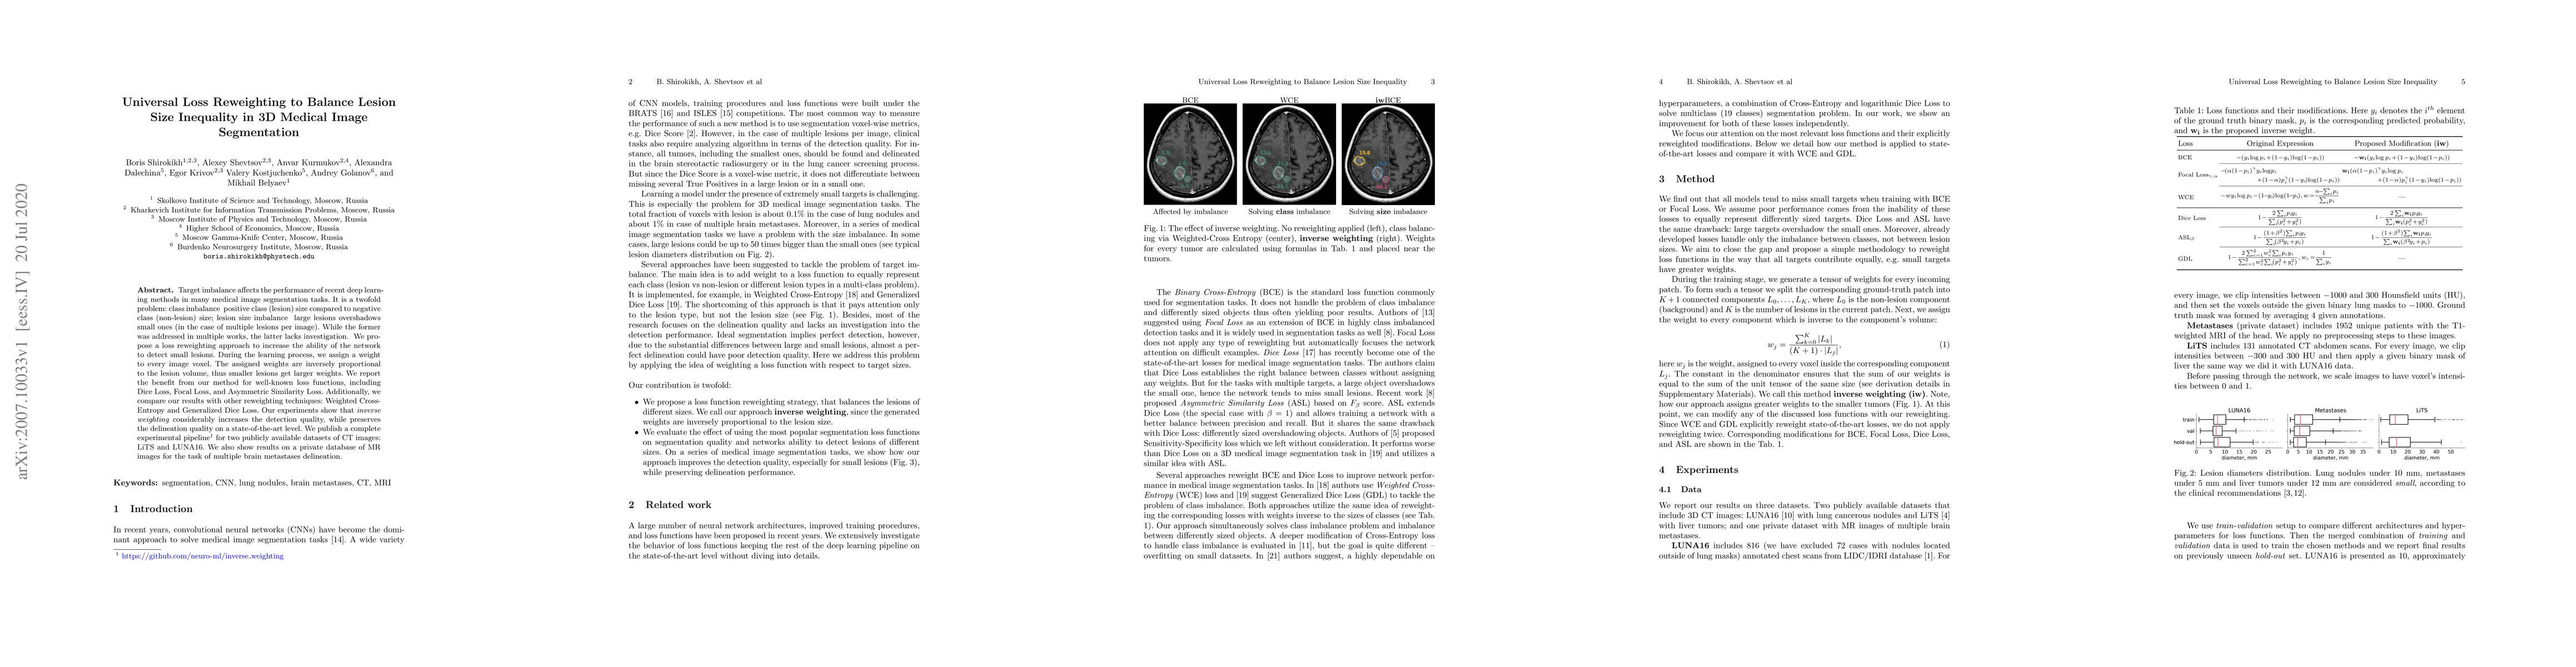

Target imbalance affects the performance of recent deep learning methods in many medical image segmentation tasks. It is a twofold problem: class imbalance - positive class (lesion) size compared to negative class (non-lesion) size; lesion size imbalance - large lesions overshadows small ones (in the case of multiple lesions per image). While the former was addressed in multiple works, the latter lacks investigation. We propose a loss reweighting approach to increase the ability of the network to detect small lesions. During the learning process, we assign a weight to every image voxel. The assigned weights are inversely proportional to the lesion volume, thus smaller lesions get larger weights. We report the benefit from our method for well-known loss functions, including Dice Loss, Focal Loss, and Asymmetric Similarity Loss. Additionally, we compare our results with other reweighting techniques: Weighted Cross-Entropy and Generalized Dice Loss. Our experiments show that inverse weighting considerably increases the detection quality, while preserves the delineation quality on a state-of-the-art level. We publish a complete experimental pipeline for two publicly available datasets of CT images: LiTS and LUNA16 (https://github.com/neuro-ml/inverse_weighting). We also show results on a private database of MR images for the task of multiple brain metastases delineation.